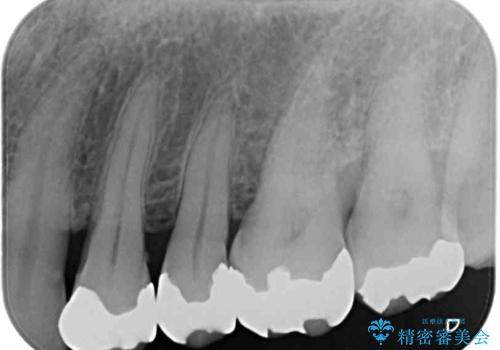

- 奥歯の銀歯をセラミックの白い歯にして、しみる症状も改善したいとのことで来院された患者様です。

知覚過敏の症状が強い歯と、銀歯の範囲や銀歯の下のむし歯が大きい歯は、インレー修復では対応が難しいためオールセラミッククラウンで、インレー修復で対応が可能な歯ではセラミックインレーにて修復することとしました。